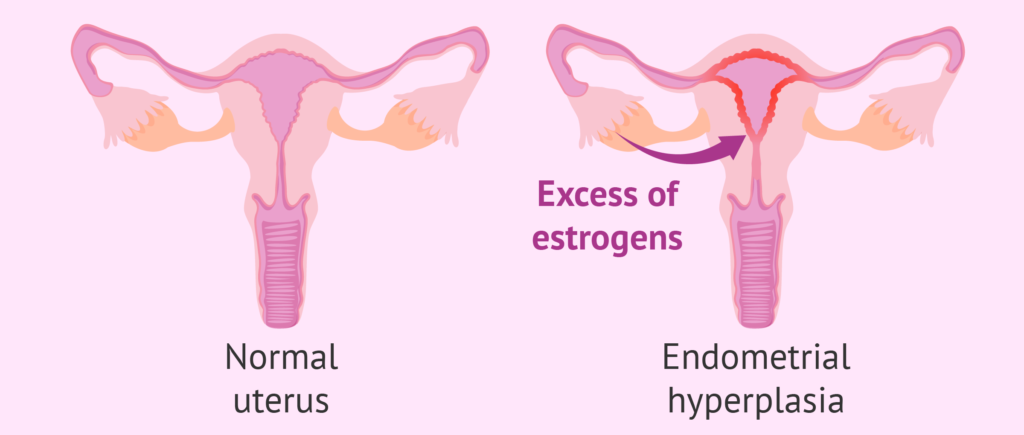

Uterine Cancer

Uterine Cancer – usually presents with heavy irregular vaginal bleeding. Hence it is usually diagnosed in early stages. But there does exist a pre-cancerous condition which is called Endometrial Hyperplasia. This is the result of excessive growth of the inside lining of the womb and is caused by excessive oestrogen hormone stimulation. The bleeding is usually very heavy during periods and can last unusually long, there can also be bleeding in between periods. That is why, if you have heavy periods your doctor would suggest a hysteroscopy and endometrial biopsy- so that endometrial hyperplasia an be detected and treated before it progresses to malignancy.